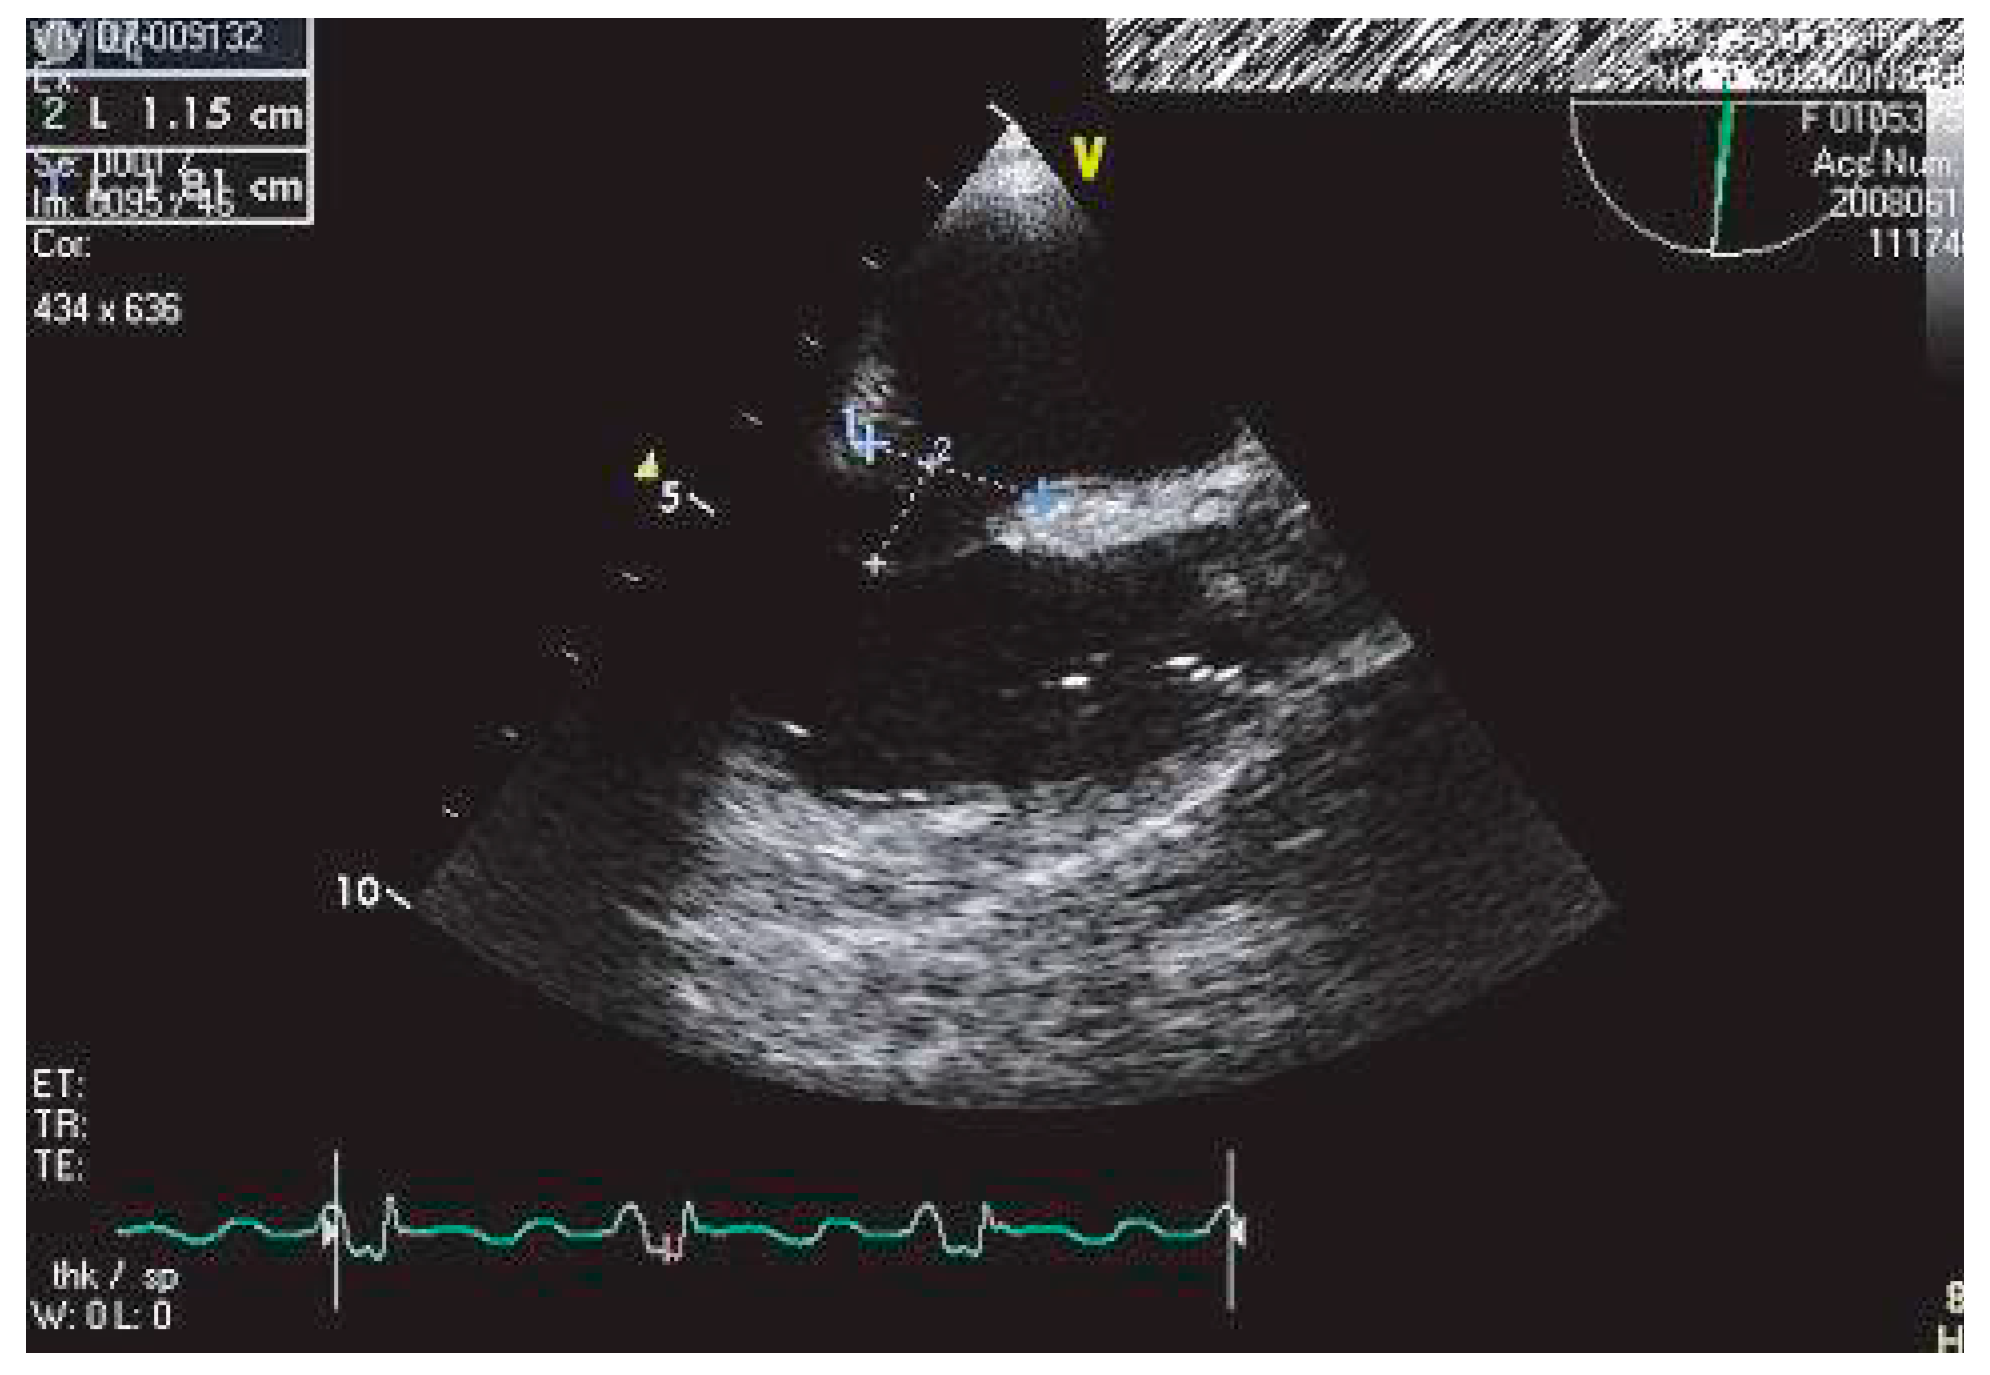

L’étude SPAF III a pris en compte des facteurs échographiques transœsophagiens afin de mieux préciser le risque thromboembolique artériel: présence d’une dilatation de l’auricule gauche, d’un contraste spontané (CS) ou d’un thrombus dans l’oreillette et l’auricule gauches (Figure 1), basses vélocités dans l’auricule gauche, présence d’un athérome aortique protrusif d’épaisseur ≥4 mm.

Figure 1. Thrombus auriculaire gauche chez une patiente en fibrillation auriculaire, visualisé en ETO à 58 degrés.